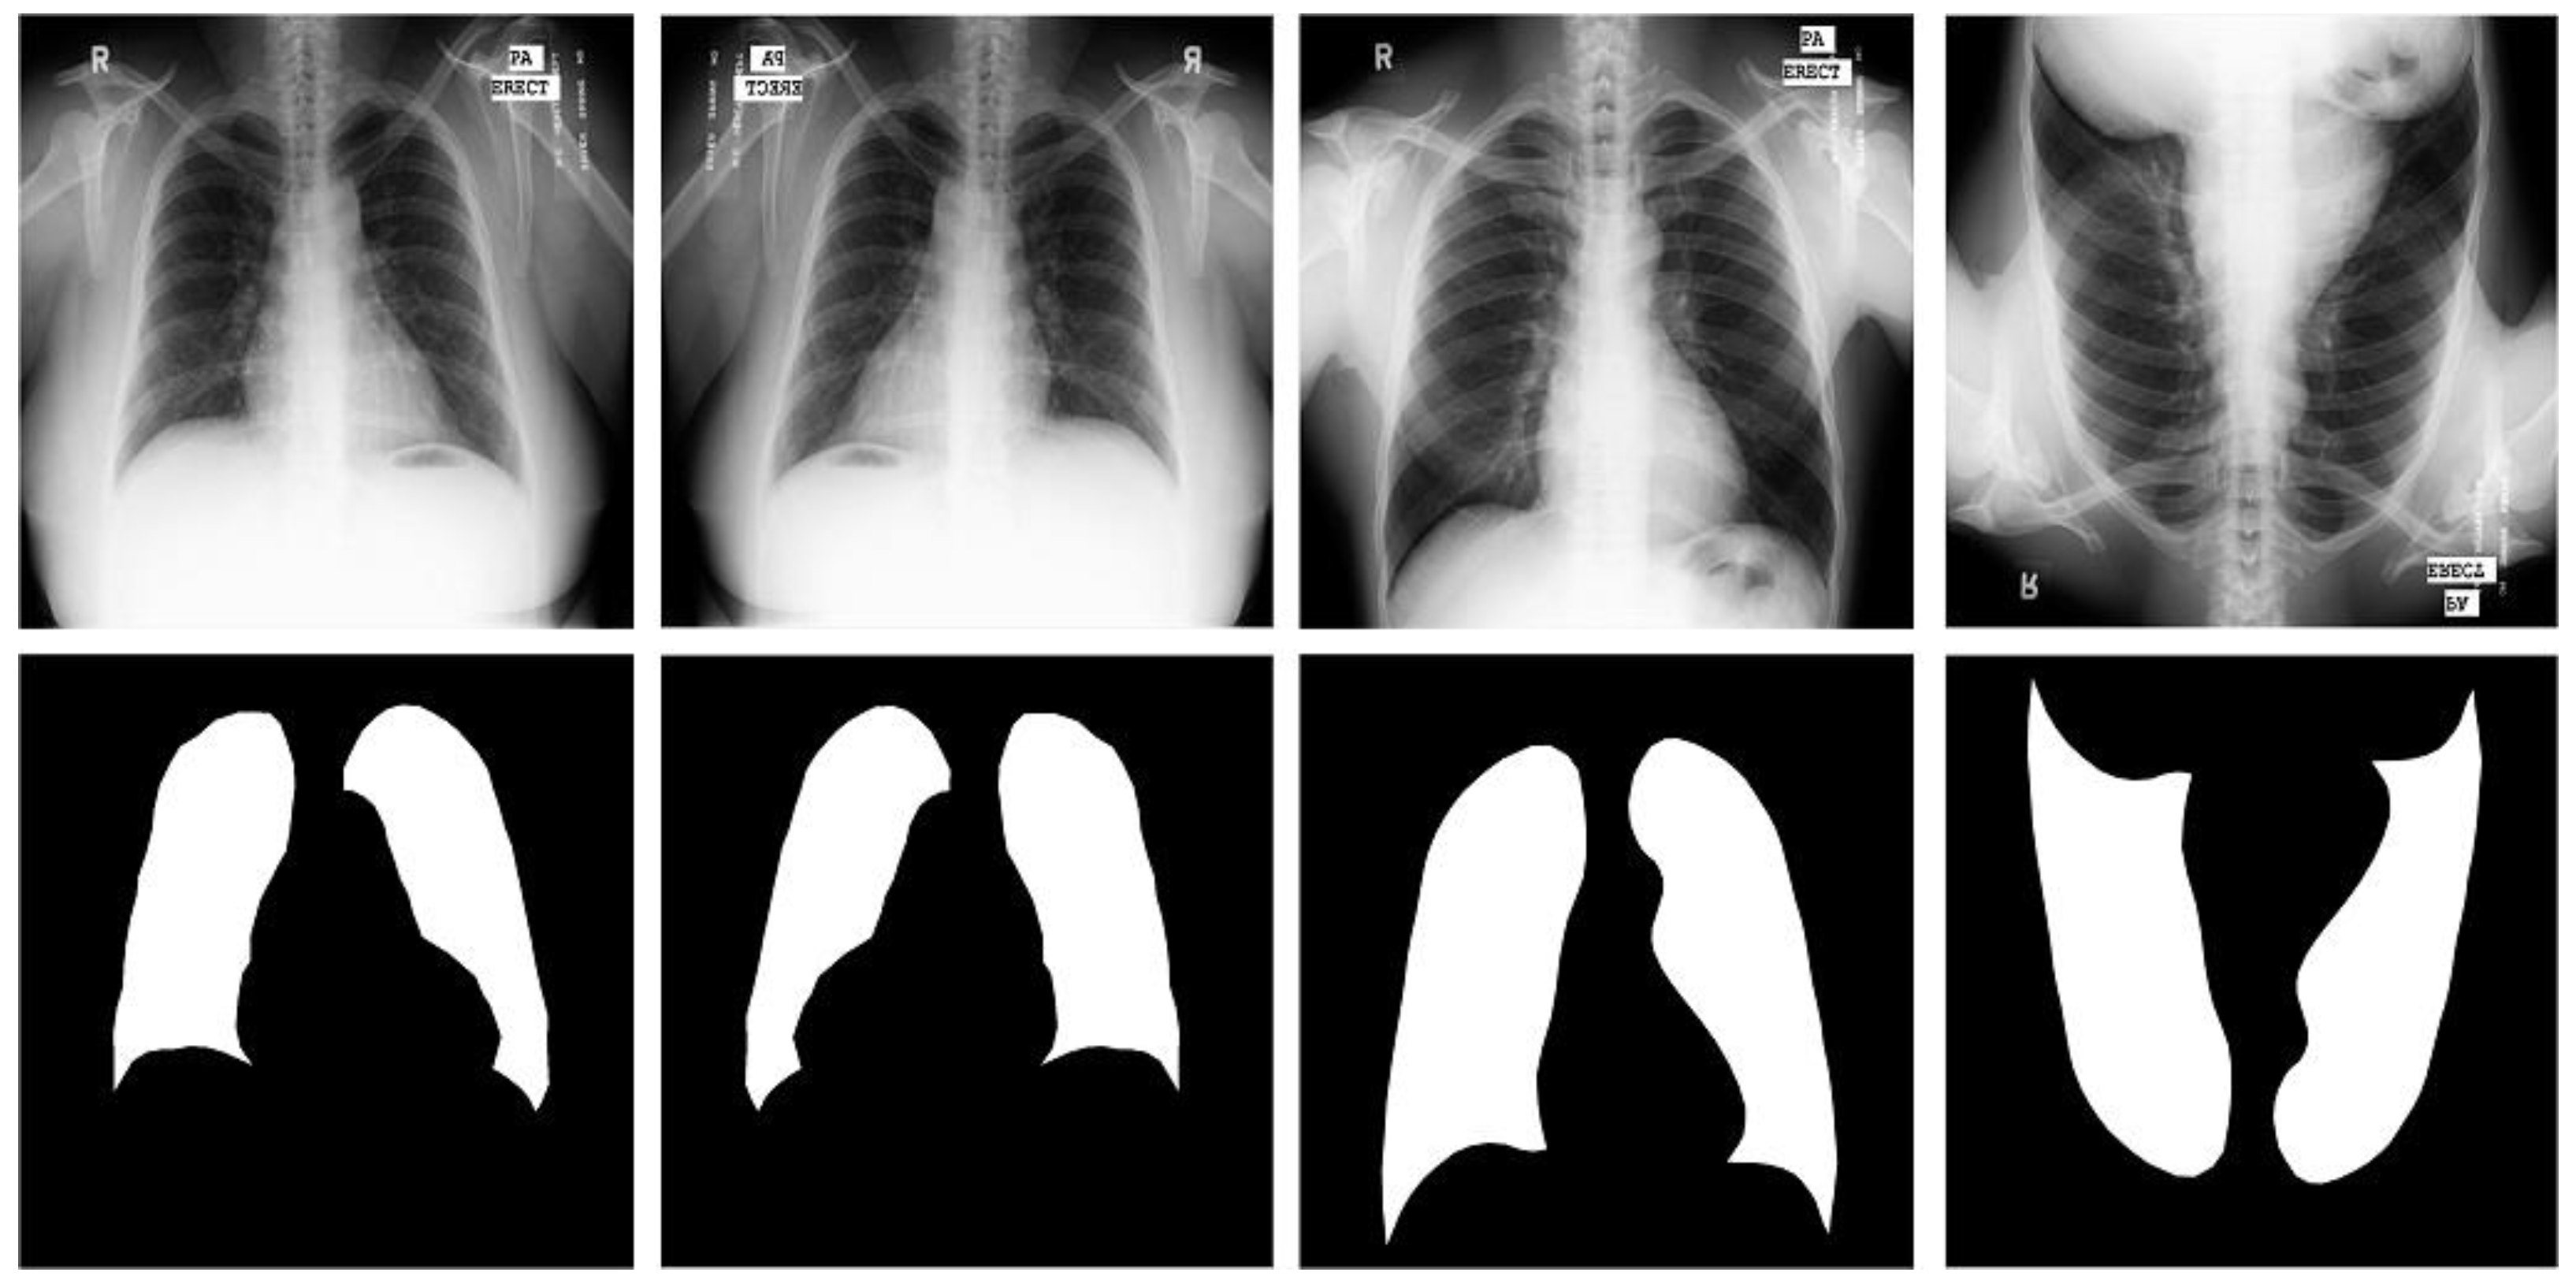

Figure 3.

Images and masks of the JSRT dataset.

JSRT dataset [16]. One of the datasets we used was created in 1998 by the Japanese Society of Radiological Technology in collaboration with the Japanese Radiological Society (JRS). It contains 247 PACXR images of the human chest region. Each CXR line slice is a single-channel grayscale image with a color depth of 8 and has a resolution of ; 154 have pulmonary nodules and 93 are normal. In order to ensure the universality of the dataset and prevent training overfitting, we used two simple three-fold random rotations and three-fold flipped data enhancement strategies, and inserted the original image data into the expanded dataset together with the training to obtain the original seven-fold dataset number and 1729 images. We used 1400 images as training cases, 140 images as test cases, and 140 images as validation cases. In the JSRT dataset, we used the segmented chest slice SCR dataset [30], because the lung segmentation mask in it corresponded to the JSRT dataset.